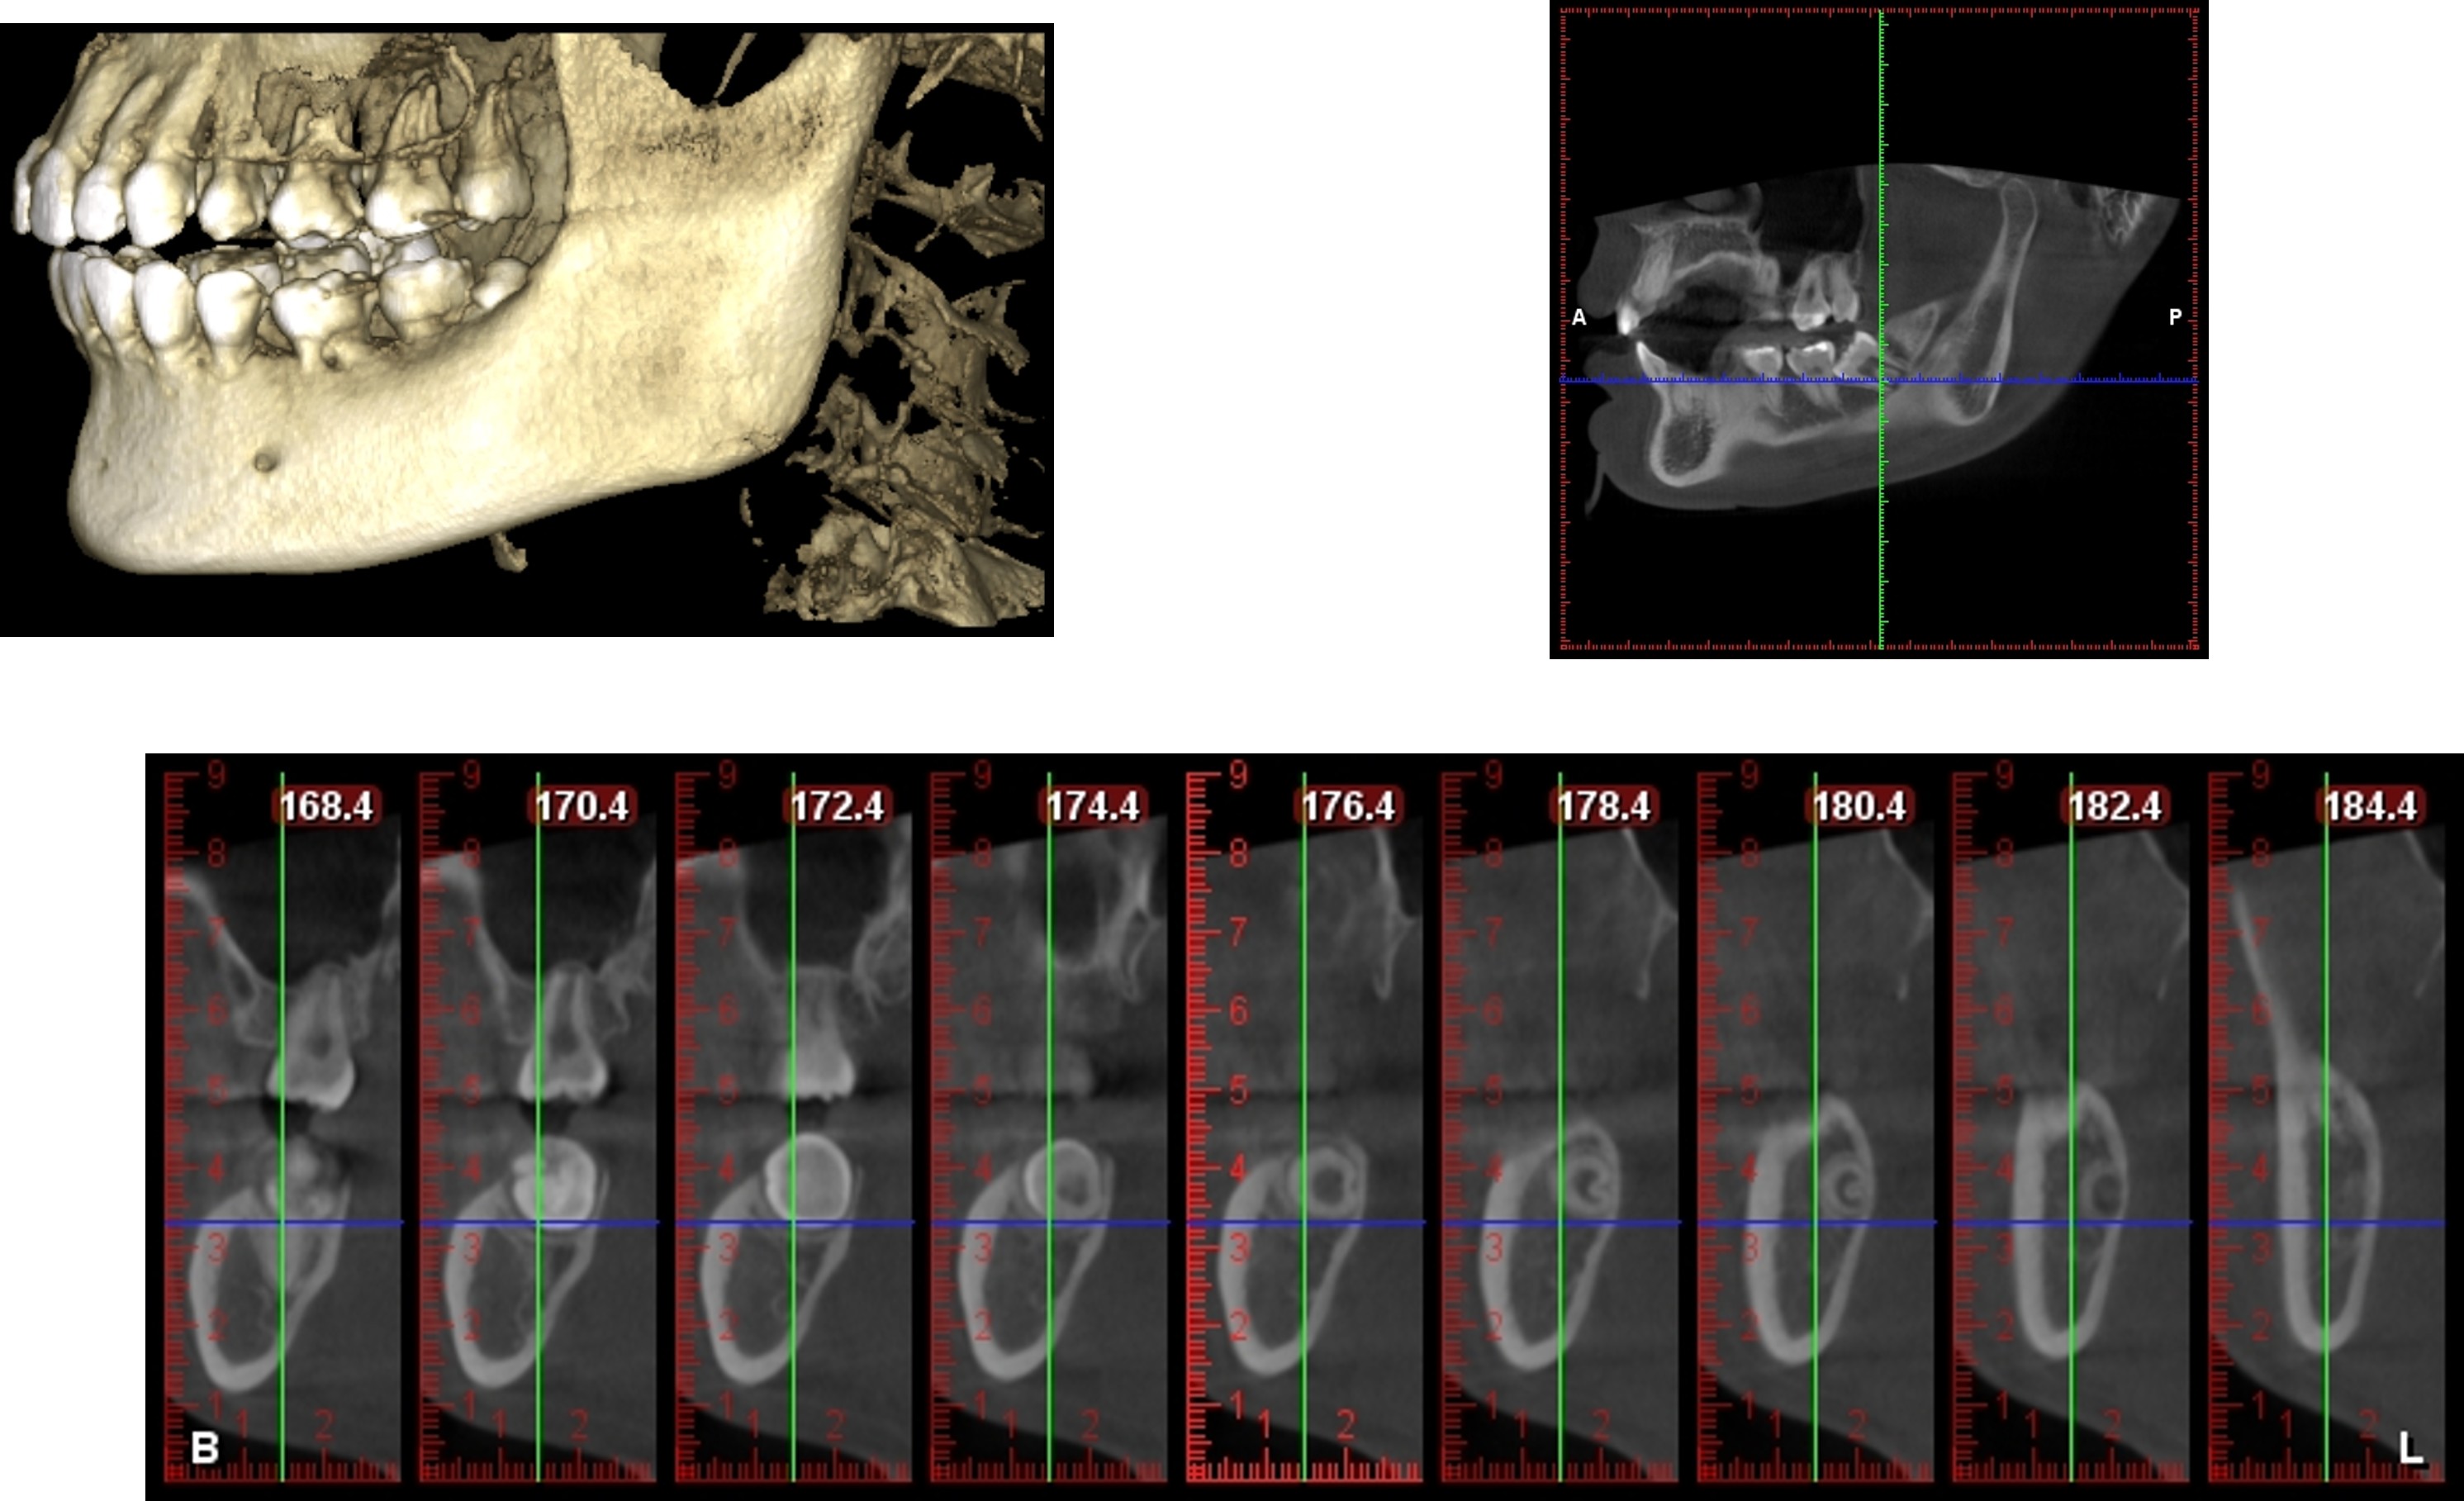

電腦斷層檢查

以電腦斷層檢查牙齒位,與鄰近神經